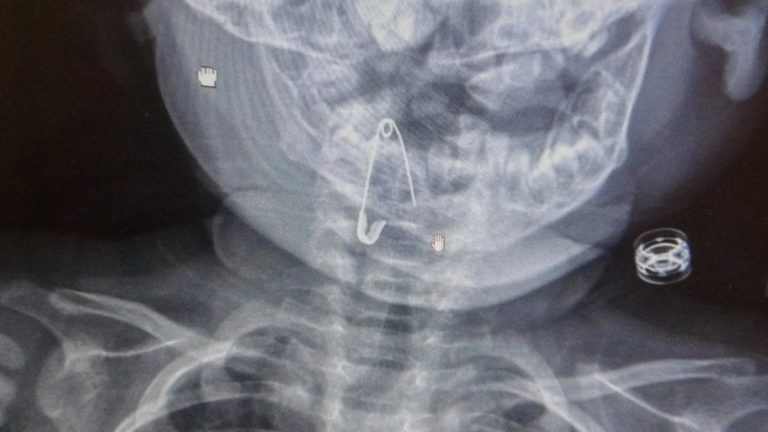

Öksürmeye başlayan minik çocuğun, hastanede çekilen röntgen sonucu çengelli iğneyi yuttuğu fark edildi.

Çengelli iğnenin saplı olduğu soluk borusundan çıkarılan bebek, 2 saatlik gözlemin ardından taburcu edildi.

8 aylık bir bebek, Bitlis’in Güroymak ilçesinden tarafımıza danışıldı. Güroymak ilçesinde çekilen röntgen sonucunda çengelli iğnenin soluk borusunun girişinde olduğunu teyit ettik. Yapılan müdahaleler sonucunda çengelli iğneyi çıkardık. Çıkardıktan sonra iki saat kadar gözlem altında tuttuk hastamızı. Daha sonrasında herhangi bir komplikasyonla karşılaşmadık ve sorunsuz bir şekilde taburcu ettik.